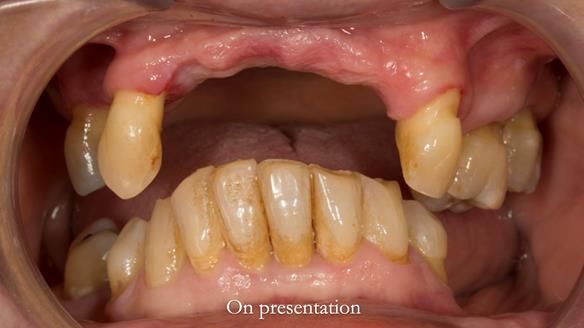

In this edition, I present the removable partial denture treatment for Jean, an 80-year-old woman with a sore mouth caused by a soft tissue-supported 'gum stripper' acrylic denture and a clenching habit. Below, I outline the step-by-step process of her treatment. It wasn't straightforward; I had to remake the denture after it fractured to achieve a satisfactory result. Each patient is unique, and sometimes a new RPD serves as a prototype. Occasionally, I need to make adjustments, learn from any mistakes, and refine the design to get it right.

The treatment has been a success over the past 4 years.